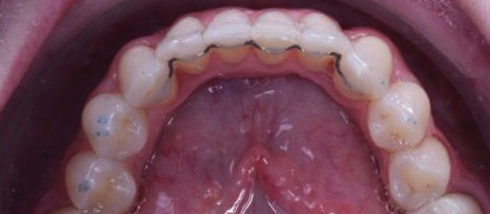

Lower severe crowding

Lower front teeth tend to respond very well to orthodontic treatment using invisalign